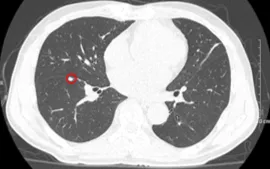

Ung thư phổi nằm trong nhóm bệnh ung thư gây tử vong cao hàng đầu. Đáng lo ngại, giai đoạn sớm bệnh thường diễn tiến âm thầm, ít triệu chứng. Khi xuất hiện biểu hiện rõ rệt, bệnh có thể đã tiến triển nặng, ảnh hưởng lớn đến cơ hội điều trị.

Theo các bác sĩ Bệnh viện Phạm Ngọc Thạch (TP Hồ Chí Minh), nhiều trường hợp đến khám khi bệnh đã ở giai đoạn muộn do chủ quan với các triệu chứng hô hấp kéo dài. Việc phát hiện sớm đóng vai trò quan trọng trong nâng cao hiệu quả điều trị và kéo dài thời gian sống.

Chuyên gia khuyến cáo, người hút thuốc lá, làm việc trong môi trường ô nhiễm, có bệnh phổi mạn tính hoặc tiền sử gia đình mắc ung thư phổi nên tầm soát định kỳ. Khi có các dấu hiệu bất thường như ho kéo dài, khó thở, đau ngực hoặc sụt cân nhanh, cần đi khám sớm để được chẩn đoán kịp thời.